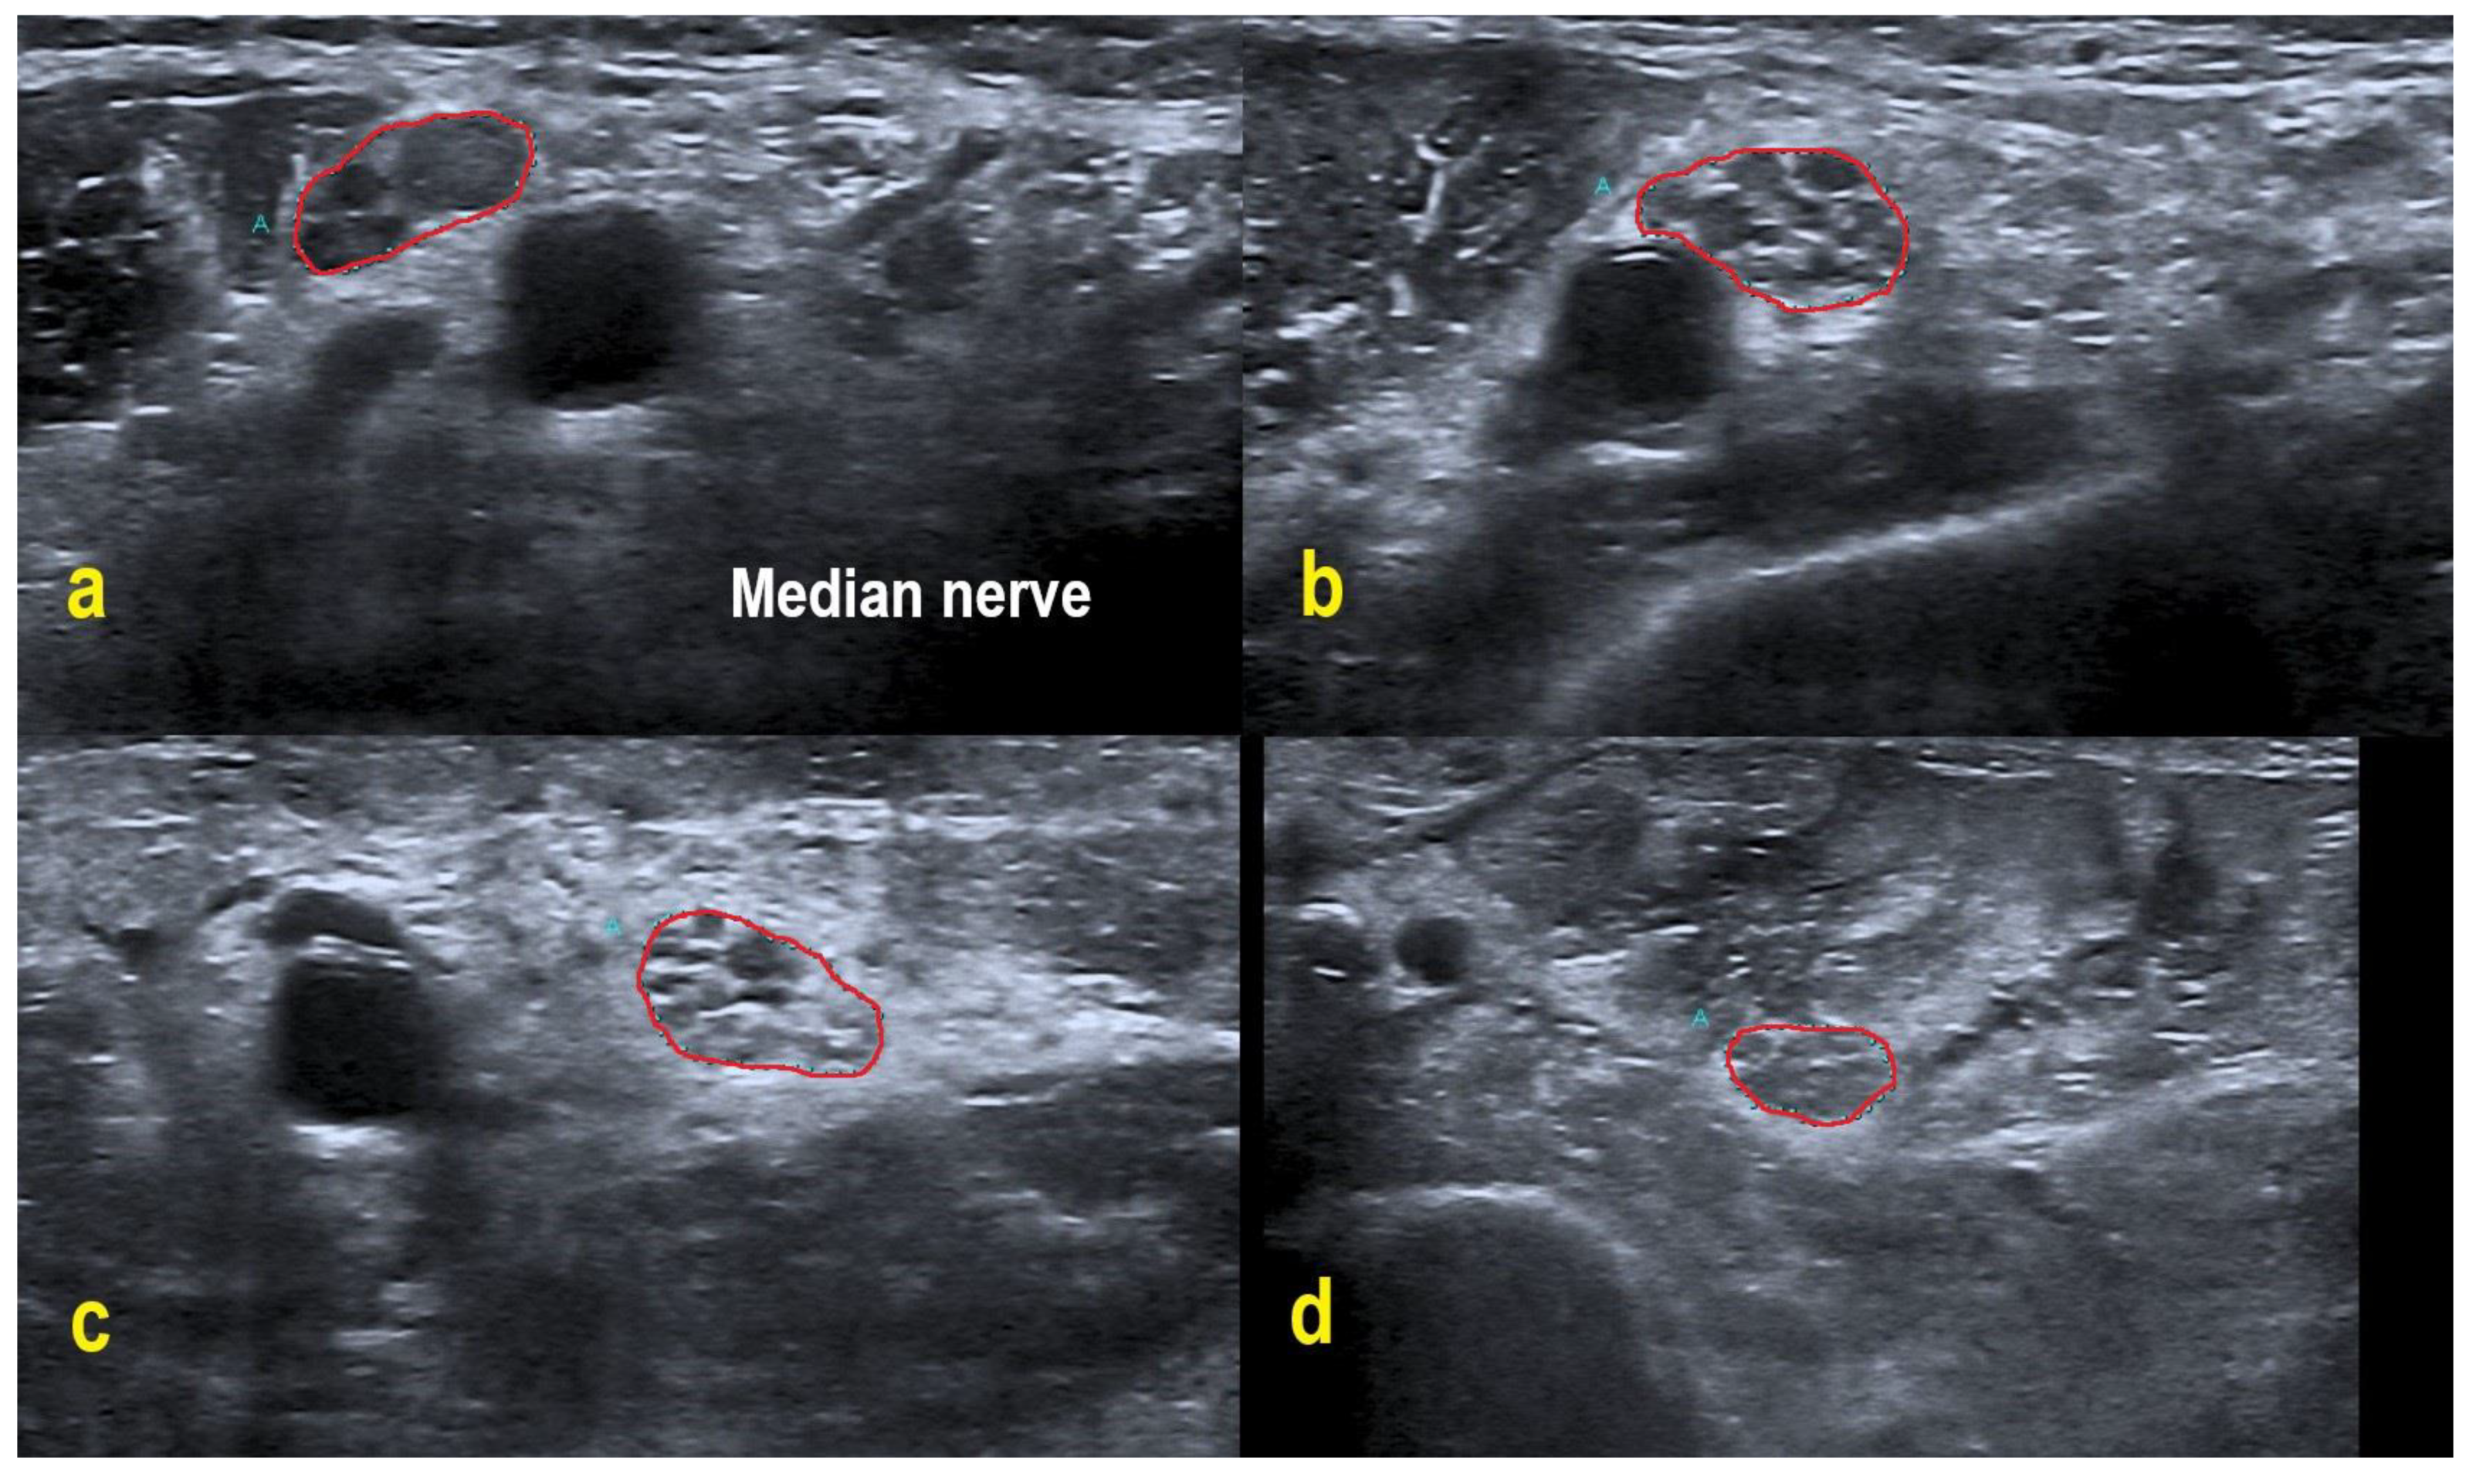

POEMS patients demonstrated overt homogeneous (two patients) and regional enlargement (one patient) in the median nerve, while CIDP patients had overt homogeneous (five patients), inhomogeneous (two patients), regional (two patients) and mild homogeneous (one patient) enlargement patterns. HRUS findings of the right median nerve in POEMS syndrome patient #3 are shown in Figure 2. Enlargement patterns in the ulnar nerve were equally heterogeneous. Two POEMS syndrome patients exhibited inhomogeneous and another mild homogeneous enlargement, five CIDP patients had overt homogeneous, two inhomogeneous, one mild homogeneous and one regional enlargement (and also one patient without an enlargement pattern).

Figure 2. HRUS in POEMS syndrome patient #3. HRUS demonstrated overt homogeneous enlargement of the CSA in the right median nerve (within red border; CSA up to 2.0-fold increased). Axilla (a): CSA 20 mm². Upper arm (b): 25 mm². Midarm (c): 23 mm². Forearm (d): 15 mm². Of note, the intraneural echointensity reflects hyperechoic interfascicular tissue next to hypoechoic fascicles.